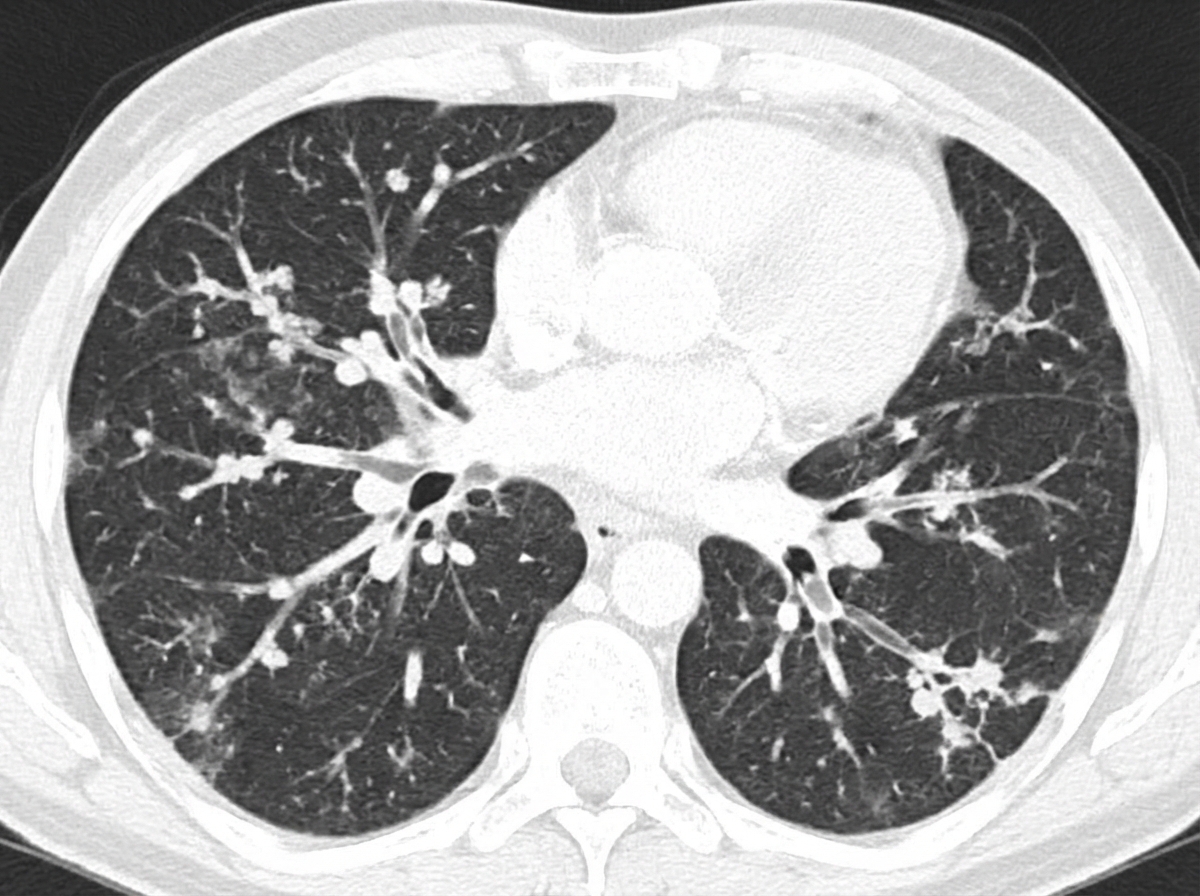

An axial HRCT of the chest is shown. The image demonstrates small peripheral branching opacities due to mucoid impaction of contiguous branching bronchioles. What is the most likely diagnosis?

Explanation: ***Endobronchial tuberculosis*** - The HRCT shows **bronchiolar dilatation, wall thickening, and mucoid impaction** of contiguous branching bronchioles — the hallmarks of **endobronchial TB** - This produces the classic **"tree-in-bud" appearance**: small, branching peripheral opacities on CT resembling a budding tree - Endobronchial TB results from direct spread of mycobacteria to the bronchial mucosa, causing caseous necrosis, ulceration, and luminal narrowing *Allergic bronchopulmonary aspergillosis (ABPA)* - ABPA can also cause mucoid impaction but typically involves **central (proximal) bronchi** with **high-attenuation mucus plugs**; associated with asthma and eosinophilia - Does not classically produce the peripheral tree-in-bud pattern *Pulmonary alveolar proteinosis* - PAP characteristically shows the **"crazy paving" pattern** on CT — geographic ground-glass opacities with superimposed interlobular septal thickening - Tree-in-bud is not a feature of PAP *Sarcoidosis* - Sarcoidosis typically produces **perilymphatic nodules**, bilateral hilar lymphadenopathy, and may show the "galaxy sign" or beaded fissure sign - Tree-in-bud pattern is not characteristic of sarcoidosis